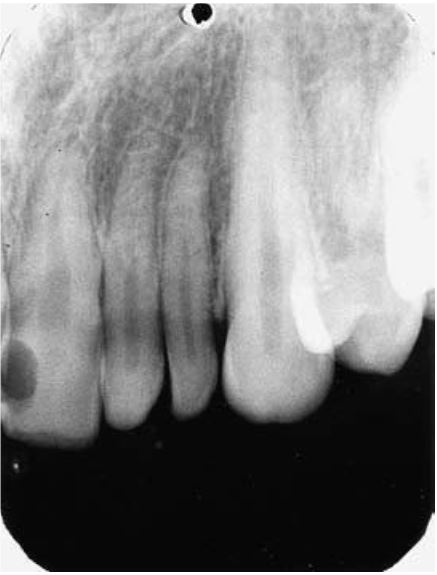

Chân răng gấp khúc

Chân răng bị gấp khúc, tạo góc >20 độ so với thân răng. Chân răng gấp khúc hay gặp khi răng chen chúc, chấn thương, tổn thương xương răng kế bên hoặc do lực chỉnh nha. Chân răng có thể phân kì khỏi thân răng theo tất cả các hướng, nhưng thường gặp nhất là theo hướng xa, xa ngoài hoặc xa trong.

Khi chân răng phân kì về phía ngoài hoặc trong thì trên X quang sẽ có hình ảnh “mắt bò”, với điểm trung tâm là ống tủy.

Chân răng gấp khúc gây khó khăn cho việc điều trị tủy, nhổ răng và chỉnh nha.